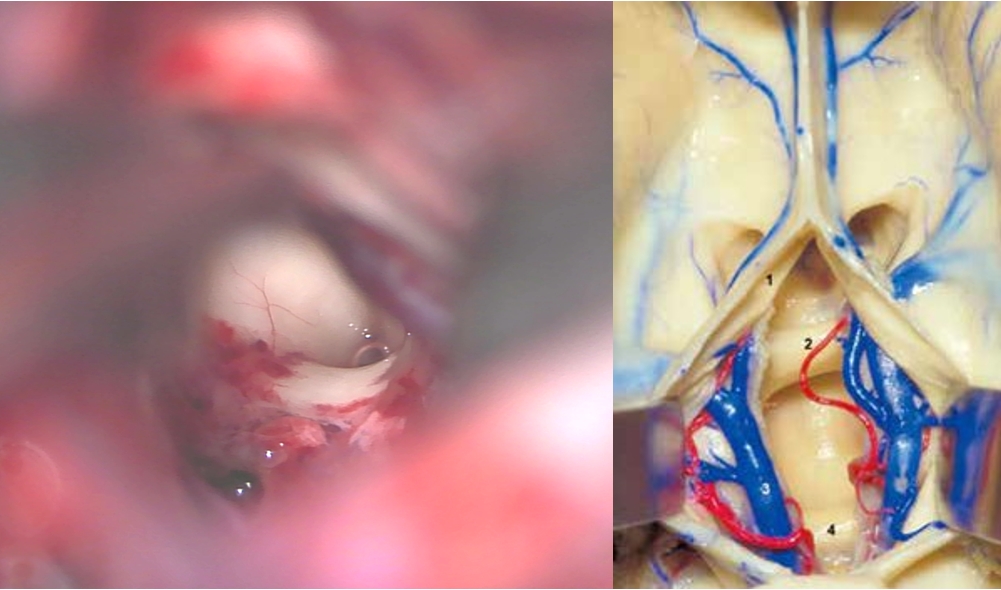

诊治过程:结合患者临床表现及影像学表现,初步诊断考虑为三脑室后部胶质瘤合并梗阻性脑积水可能性大,术前制定的手术方案为经胼胝体穹隆间入路三脑室后部肿瘤切除术+脑室镜辅助下三脑室底造瘘术,该手术方式既可切除肿瘤获取病理,同时可行三脑室底造瘘解决脑积水症状。术中采用冠状缝前额部弧形切口,术中沿纵裂牵开双侧大脑半球,探及胼胝体,沿中线切开胼胝体,分离双侧透明隔,暴露双侧穹隆,严格沿中线分离双侧穹隆,保护两侧穹隆的完整,避免引起术后的记忆力障碍,牵拉开双侧穹隆,进入中间帆,显露并分离双侧大脑内静脉继续向下,经脉络膜隔进入三脑室,完全显露肿瘤组织,肿瘤组织呈灰红色,血供极其丰富,与中脑黏连紧密,仔细分离,分块全切肿瘤,双侧大脑内静脉及中脑保护良好,中脑导水管通畅。肿瘤完全切除后,考虑到术后局部粘连、肿瘤复发等因素可能导致脑积水不缓解,置入脑室镜向前方探查,小心切开中间块,在双侧乳头体与漏斗隐窝之间,行三脑室底部造瘘并打开Liliequist膜及基底动脉旁蛛网膜,确认漏口通畅且与脚间池相通。患者术后恢复过程平稳,颅脑MRI提示肿瘤切除满意,脑积水缓解。术后病理结果示:中枢神经细胞瘤(2级)。术后予以放疗GTV 5400cGy、PTV 5040cGy,28f。现术后已3年,复查未见肿瘤复发,脑积水已完全缓解。